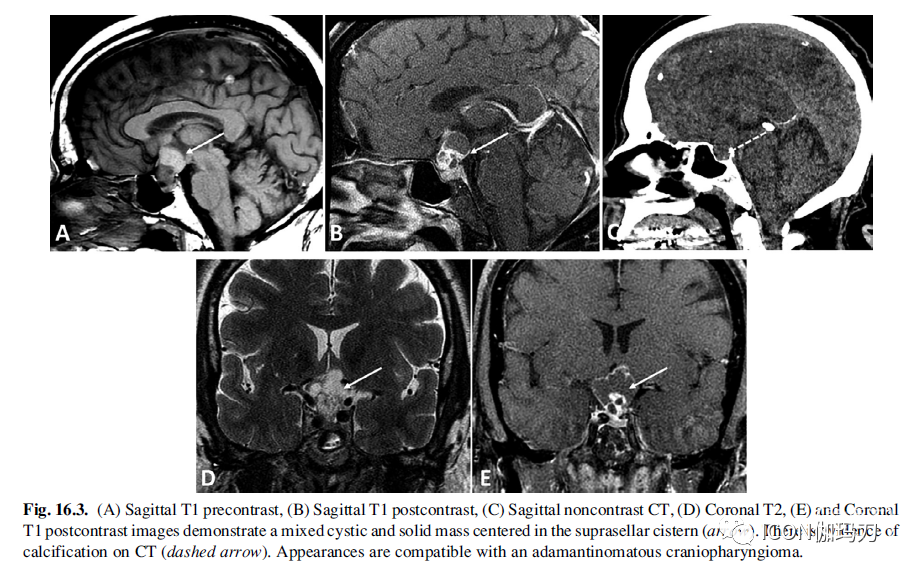

CP表现出异质性的影像学表现,大小上差异很大。造釉质型是复杂的囊性和实质性肿块,表现为不均匀强化和典型的包含有钙化(图16.3)。CT在CP的诊断中发挥着重要的作用,尤其是造釉质瘤亚型,由于高达90%的患者出现钙化和骨重塑方面的优势。钙化可能是粗糙的或点状的(coarse or stippled),可能位于囊肿壁和/或结节成分内。在CT上,囊肿密度增加,蛋白含量增加,血液产物出现。同样,囊肿在MRI上的信号强度也不同,最典型的是在T1加权、T2加权和FLAIR序列上呈高信号。囊肿不常显示液-液平面。固体成分和囊壁有不均匀质强化。钙化在T2和T2*梯度回波显像上表现最好。乳头状型CP在位置上更可能是纯鞍上型。它们是典型的球形固体肿块,表现出非均匀增强。在MRI上,乳头状CP在T加权像上最常见的是T1等信号和不均匀(图16.4)。它们可能含有小囊性成分,由于蛋白质含量低,最常见的是T1低和T2高。钙化是一种罕见的发现。CT实性成分等信号,囊性成分低信号(图16.4)。

图16.3.(A)矢状位T1平扫,(B)矢状位T1增强扫描,(C)矢状位CT平扫,(D)冠状位T2, (E)冠状位T1增强扫描显示鞍上池中心一囊实性混合肿块(箭头)。CT示钙化(虚线箭头)。外观符合造釉质颅咽管瘤。